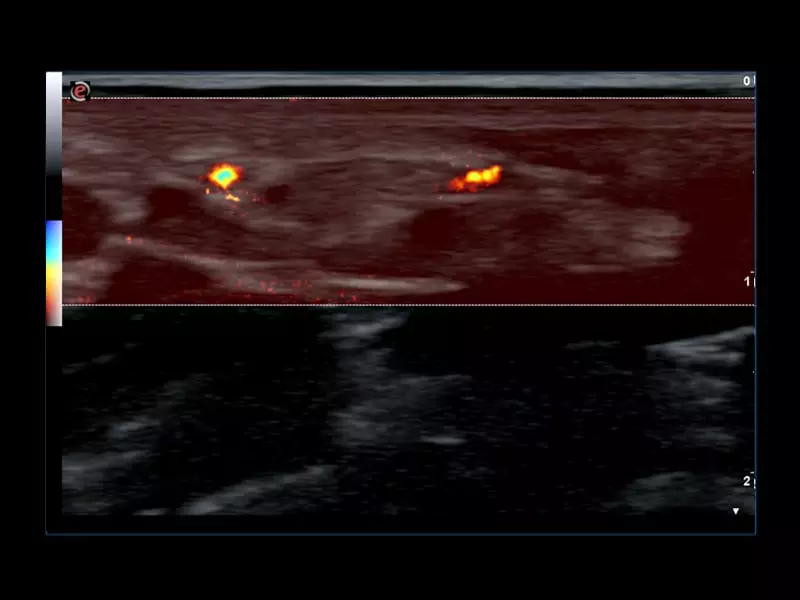

MyLab™C25 - MICRO-V-thyroid-linear

MyLab™C25 - MICRO-V-thyroid-linear